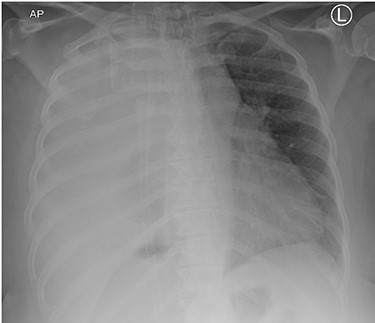

Surgery consisted of a right thoracotomy through the fifth intercostal space. The mass was found to be compressing the three lung lobes of the right lung, and no gross mediastinal invasion appreciated. Mass excised using a combination of blunt dissection and cauthery. An anterior and posterior thoracostomy tubes were left in place. Final dimensions of the mass were 19.2 cm × 17.5 cm × 10.5 cm (See Fig. 5). After mass excision right lung collapse was evident (See Fig. 6). Then after right lung ventilation, all three right lobes expanded (See Fig. 7). Postoperative CXR was also consistent with full right lung re-expansion (see Fig. 8).

Postoperative CXR revealing complete lung expansion, no associated pneumothorax, no effusion.